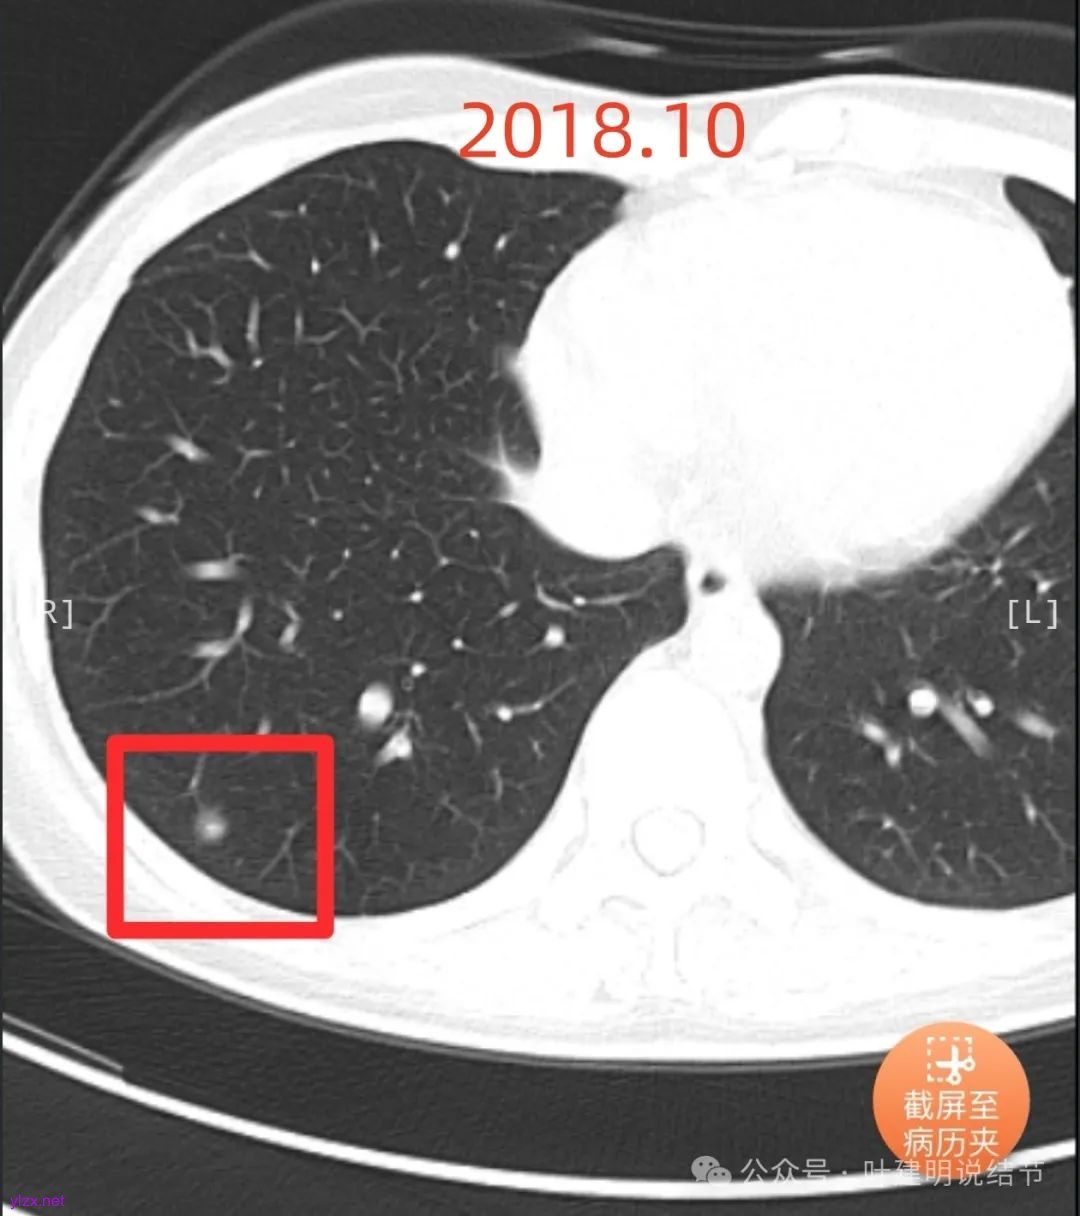

患者7年前在当地医院就诊时完善胸部CT发现肺结节,发现后未服用药物治疗,定期复查随诊,2024-09-29复查胸部CT提示:右肺下叶(薄234)见混杂密度小结节影,边缘毛糙,大小约0.8x0.7cm,其内见小血管穿行。双肺可见多发微小结节影,双肺见索条影,右肺可见小钙化灶。近期患者无咳嗽、咳痰、咯血、胸闷、胸痛、心慌、气急、头晕、头痛、畏寒、发热等不适,精神、饮食、睡眠正常,大小便正常,体重无明显变化。

2024年9月时病灶较前有所增大,实性成分增大,表面不平,棘突明显,进入血管有异常增粗。